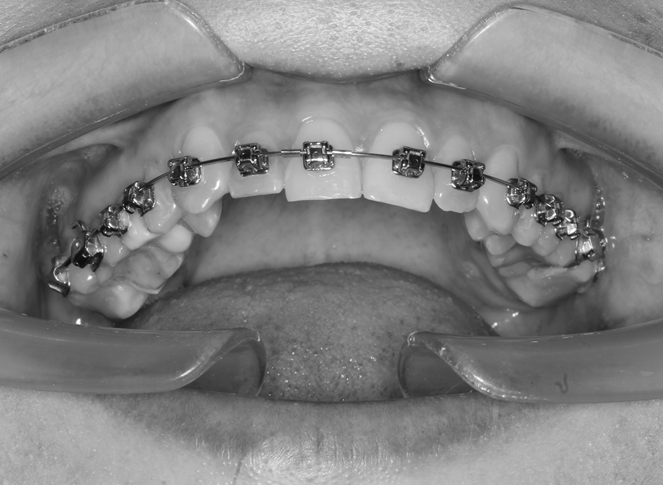

The results of the conducted studies allowed us to move on to orthodontic treatment, which consisted of the sequential application of the bracket system first to the teeth of the upper jaw; wearing of the occlusal splint continued at this stage (Fig. 6).

Fig. 6. Braces on the teeth of the upper jaw